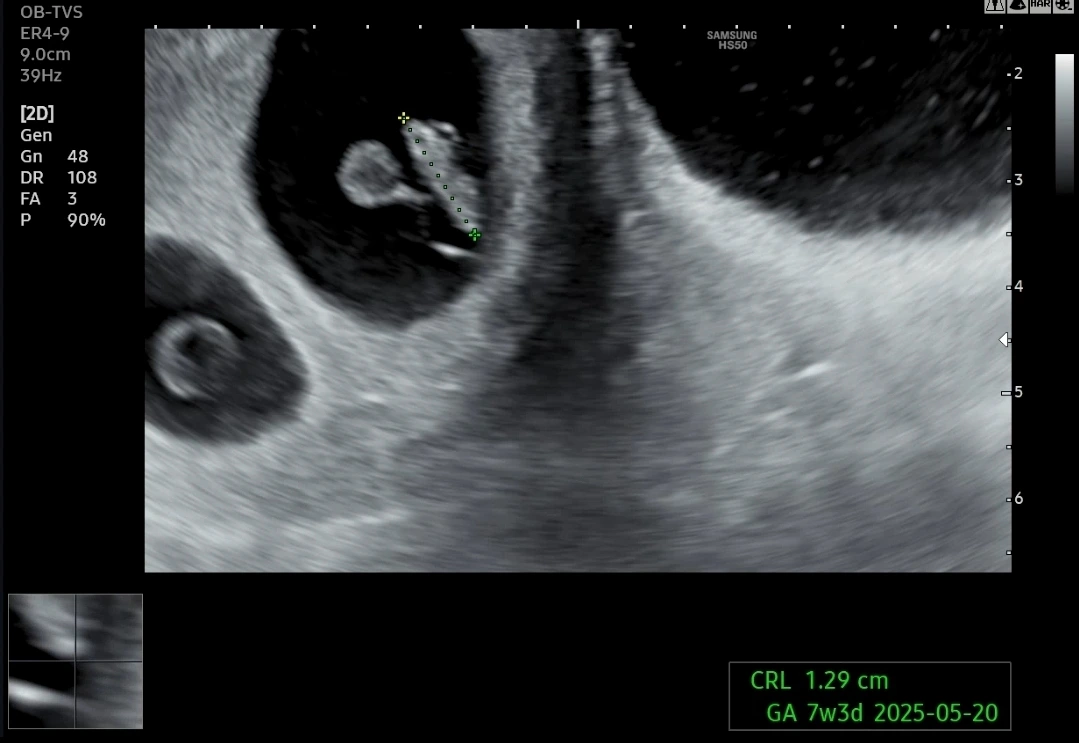

지난주 0.6cm였던 요미는 그 사이 1.3cm 정도가 되어 주수에 맞게 잘 크고 있다고 하셨다.